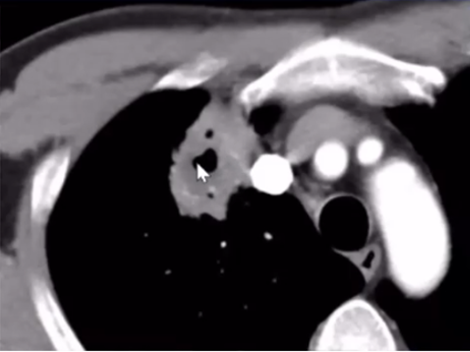

下图为一肿块,周围有晕征,中间有小气泡,增强扫描可见大片坏死,没有强化(图19),这种特征非常像曲霉感染,但最终穿刺病理证实为毛霉感染。其破坏范围更广。临床上,在诊断不清的情况下,一定要做增强扫描,能够帮助确定组织强化的程度。患者出现了胸腔积液,其中的小气泡更大,这是毛霉的特征。

图片

图19  毛霉感染

毛霉感染患者胸部CT可见反晕征,有胸腔积液,说明病变侵犯力非常强。其次,病变中的分隔粗大,其中的小气胞分布范围广。另外,病变中没有看到气液平面。但是由于病灶的破坏力更强更快,毛霉的生长跟不上,坏死物固定相对较弱,所以其病变破坏更多向外扩张,对血管的破坏性更大,因此我们看到很多低密度影。这是毛霉的特征。毛霉破坏组织后产生一些组织残留,因此CT上可见很多分隔(图20,图21)

图20  毛霉感染—反晕征,胸腔积液,分隔粗大